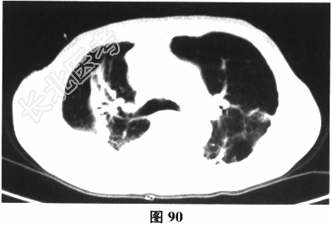

- 多项选择题3.[提示]动脉血气分析:pH7.32, PCO280mmHg,PO250mmHg, SaO285%,HCO-334mmol/L。胸部HRCT结果如图90和图91所示。